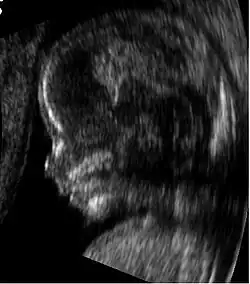

Modern 3D ultrasound images provide greater detail for prenatal diagnosis than the older 2D ultrasound technology.[6] While 3D is popular with parents desiring a prenatal photograph as a keepsake,[7] both 2D and 3D are discouraged by the FDA for non-medical use,[8] but there are no definitive studies linking ultrasound to any adverse medical effects.[9] The following 3D ultrasound images were taken at different stages of pregnancy:

3D Ultrasound of fetal movements at 12 weeks

75-mm fetus (about 14 weeks' gestational age) -

Fetus at 17 weeks -

Fetus at 20 weeks